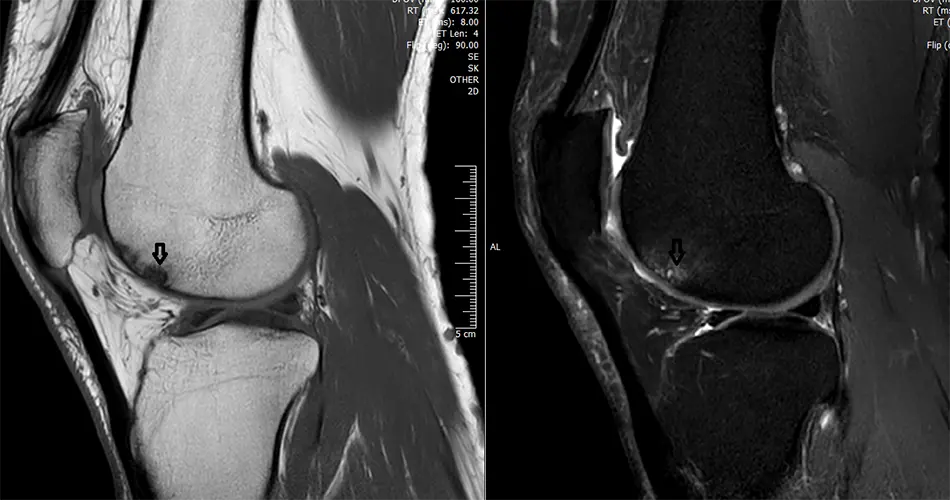

How is it diagnosed?

Clinical exam and MRI scans confirm the size and stage of the lesion.